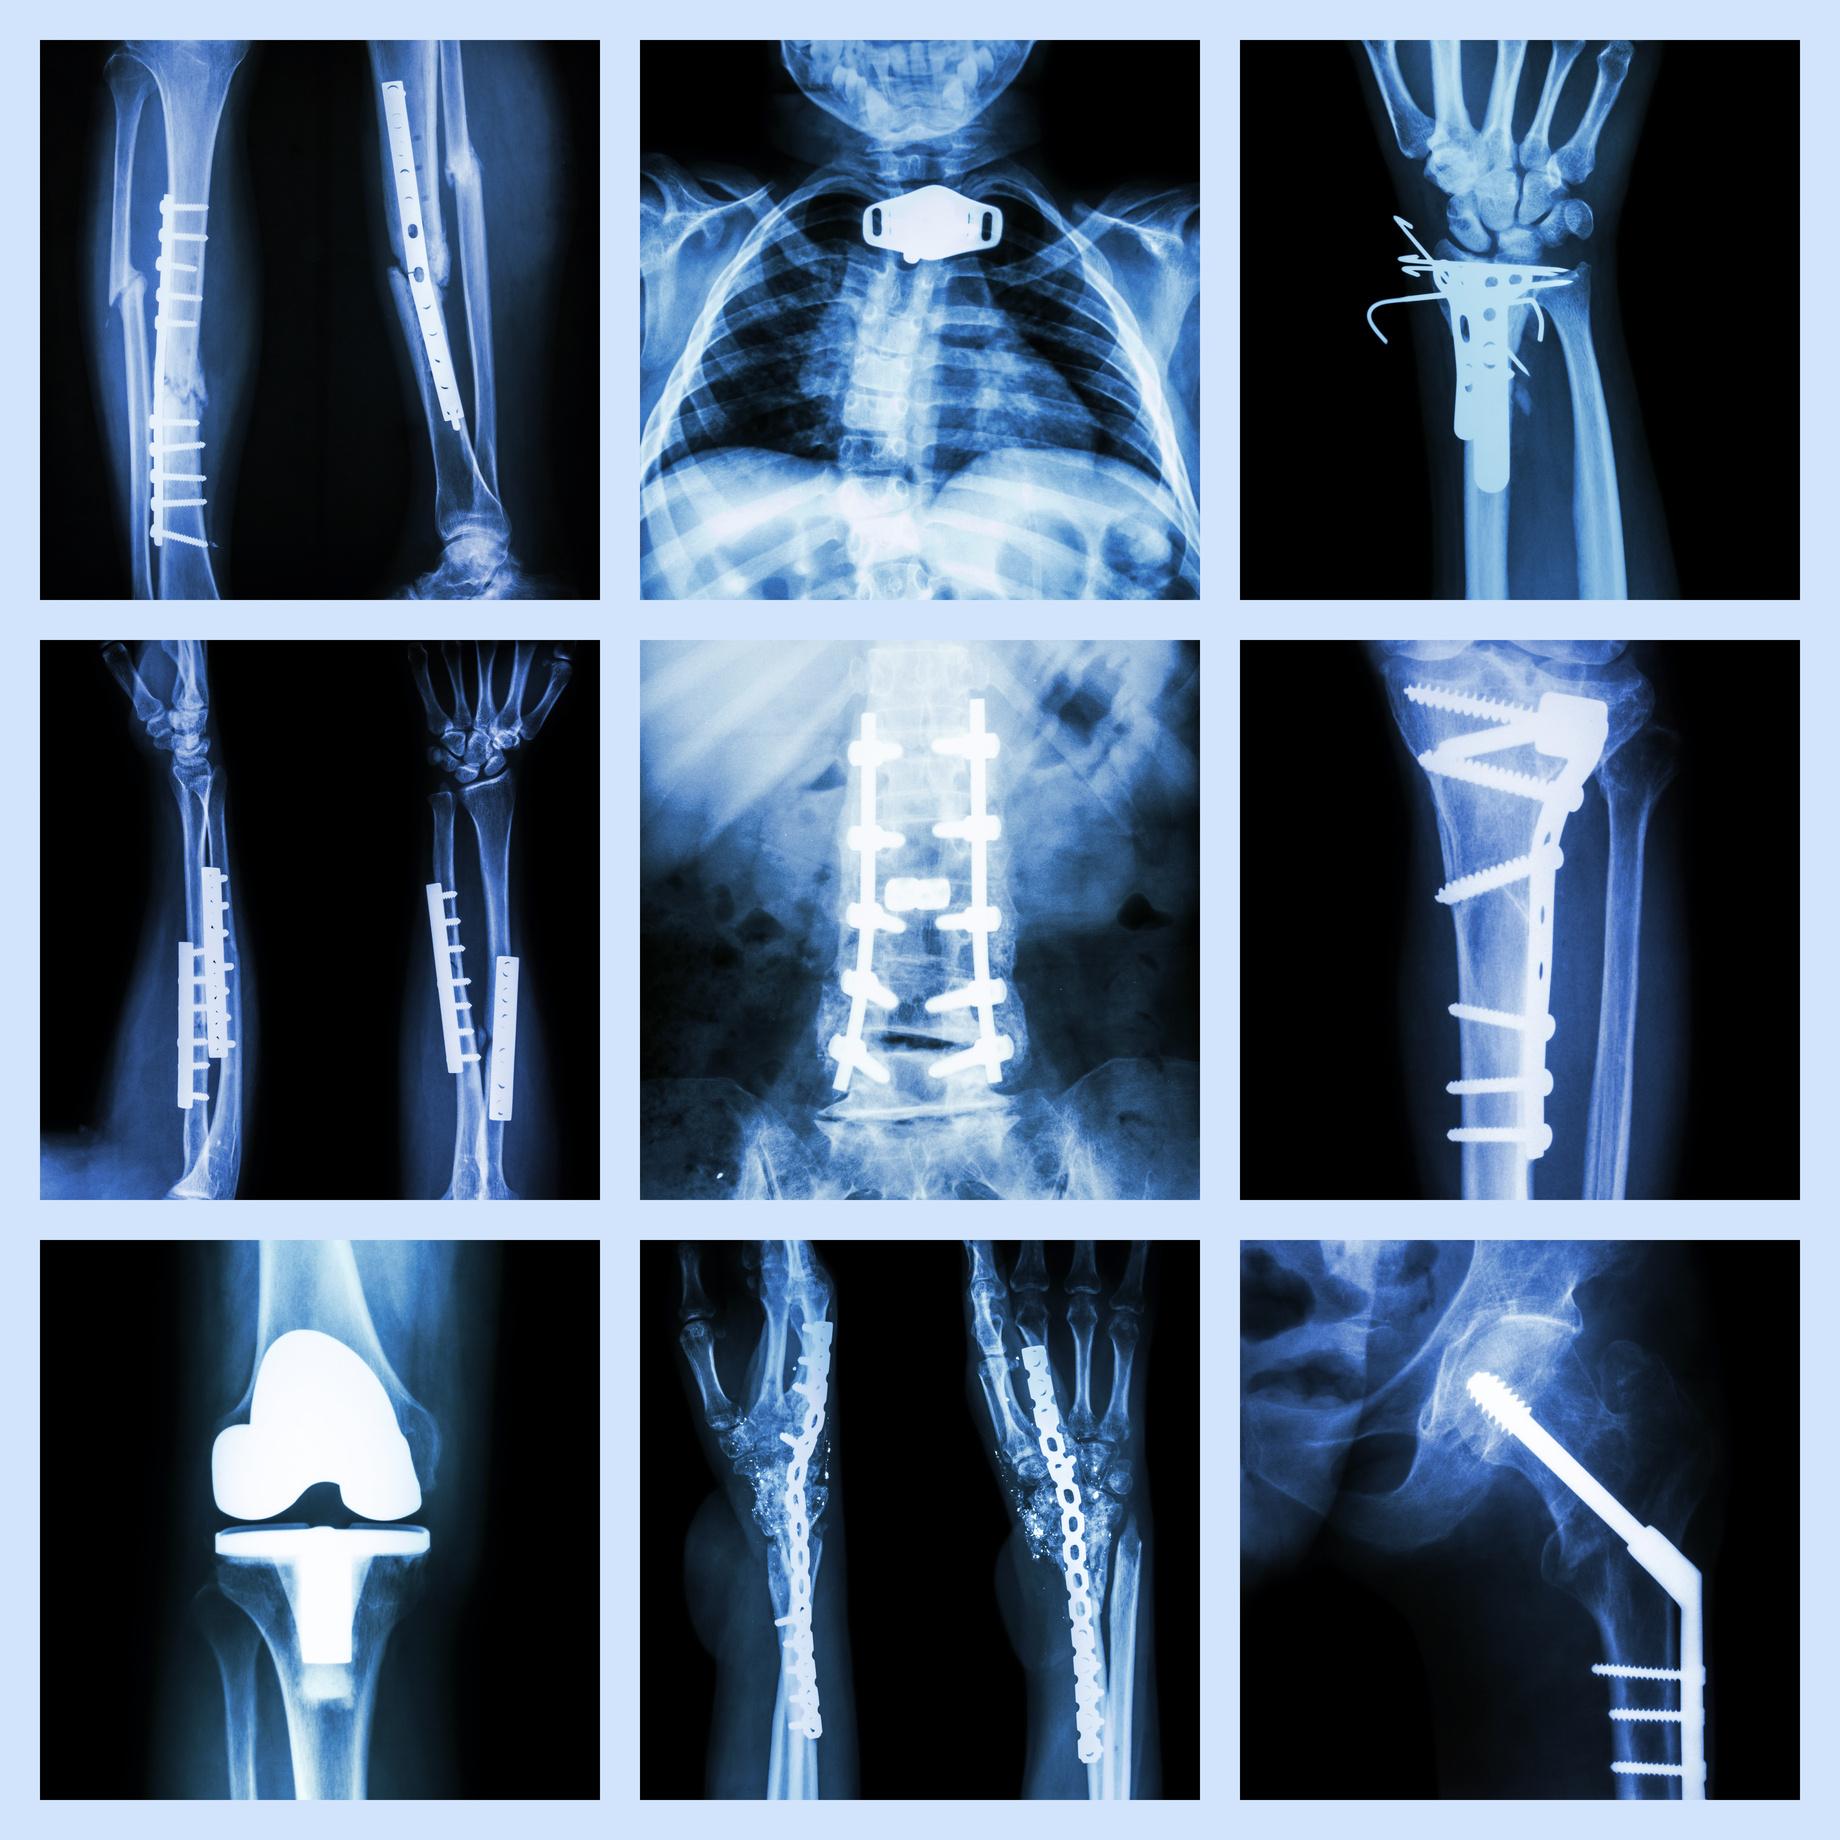

Like many doctors in the early years, Grantel Dundas’ initial interest in medicine changed from one field to another With exposure and experience being the primary influencers of change, a young Dr. Dundas would shift his previous inclination in cardiothoracic surgery to his destination career choice of orthopedic surgery. “I remember being in a lecture at the University of the West Indies and I saw a patient on whom Professor Golding had done a muscle transfer ” Dundas explains muscle transfer as the process of allowing the patient to use an arm that had been previously paralyzed because of an injury.

“The idea of working on the heart was something that thrilled me But when I saw that he (Prof Golding) made something work that couldn’t I said to myself that this is really what I want to be able to do.” Right away, cardiothoracic surgery immediately paled in Dundas’ mind, and a path formed in his head to his final choice.

Dr Grantel G Dundas is a Consultant Orthopaedic Surgeon, whose reputation for detailed excellence, paired with his impeccable social graces, lay the foundation for countless successful doctor-patient interactions that would ensue during more than five decades of practice

For Dr Dundas, his days at KPH and Bustamante Children’s Hospital as an intern and as Junior Doctor meant that one pursued the art of medicine and surgery for its own reward, which was simply ‘the satisfaction of being able to make people function well again’.

“Nothing mattered apart from the fact that our patients recovered and were able to go on with their lives.” Service above self they say, and for this stalwart, this particular period of his professional career allowed him the chance to develop his diagnostic skills, and the art of orthopaedic surgery just for itselfwithout any monetary stimulus attached to it “My reward was that I learned a tremendous amount KPH was an incredible learning ground for me.”